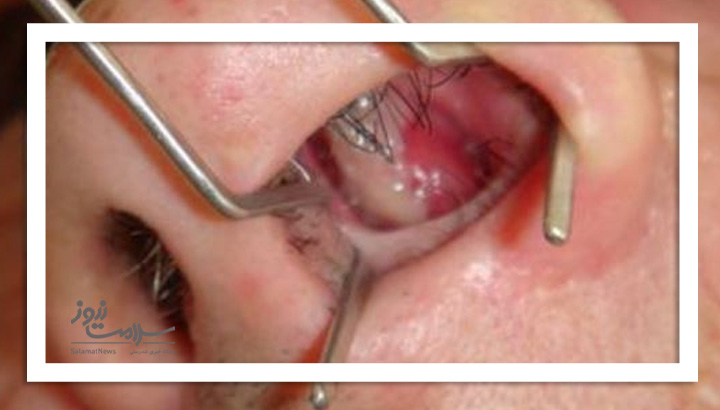

عکس زخم داخل بینی